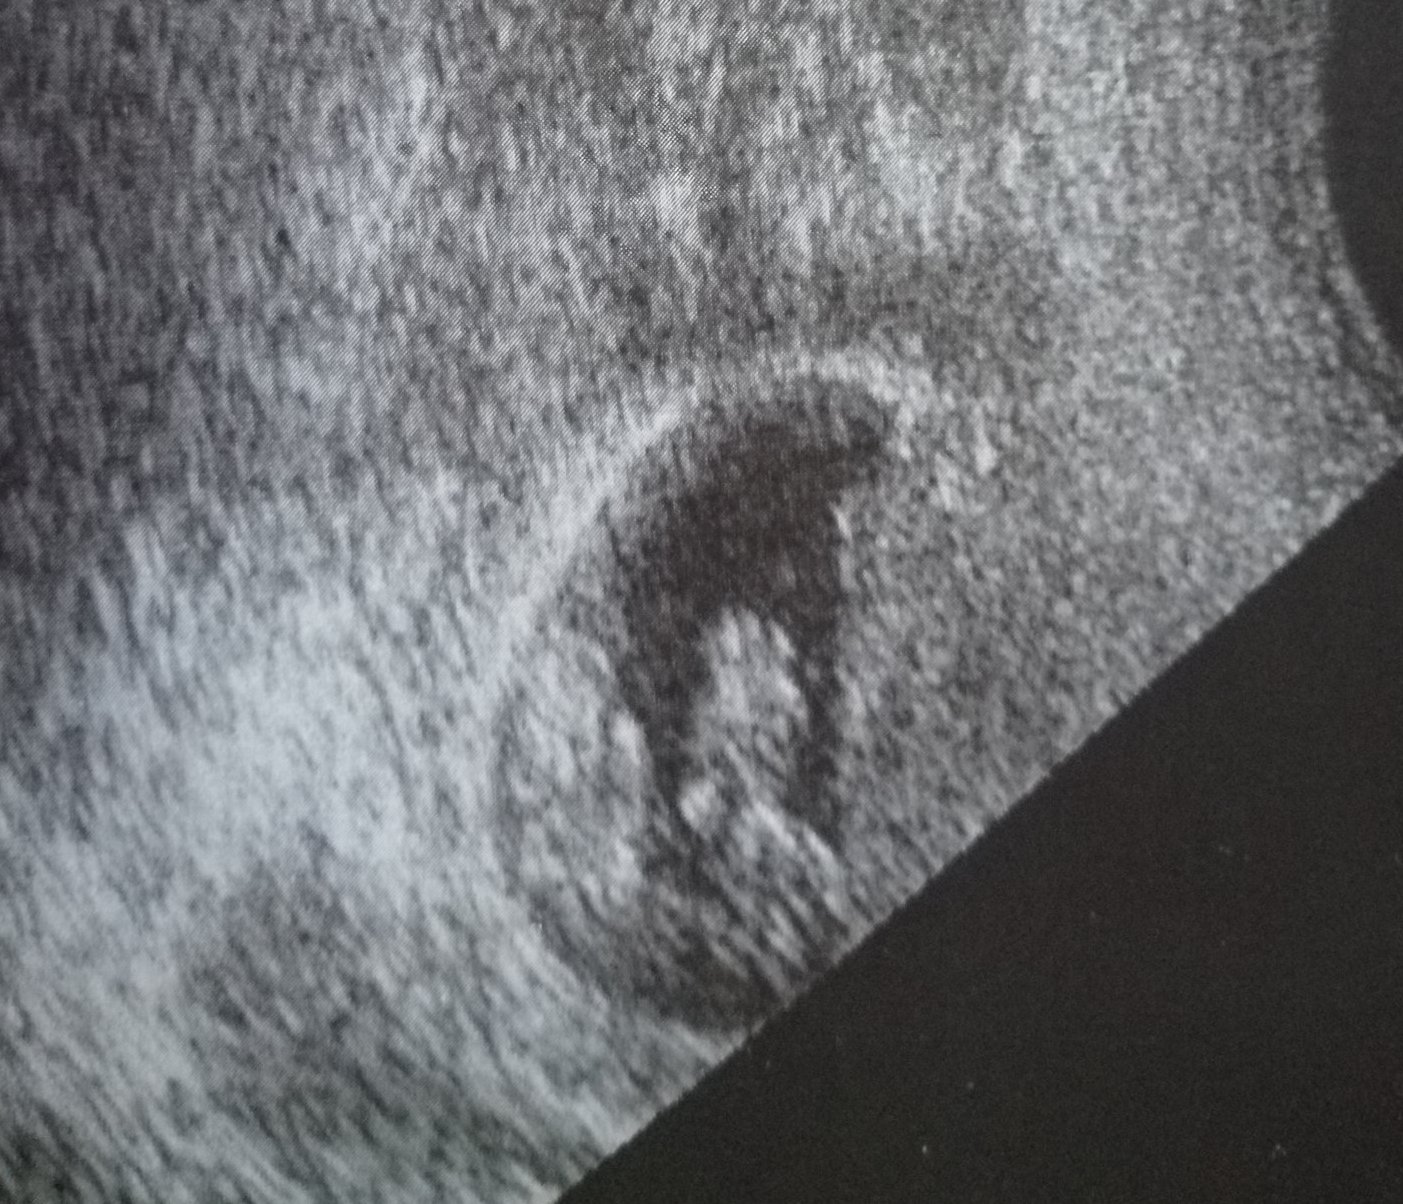

Сакчето е голямо, възможно е да са близнаци, виждат ми се 2 точки, ако са близнаци са еднояйчни. Снимката е от7 седн. .  Моите са еднояйчни и на тази снимкане разбраха, че са 2 бебета. А тази е от 11 седм.

Ако другото продълговатото е сакче са двуяйчни,  но азмисля, че е едно сакче

Kefcho91, просто за сравнение, макар, че моите са разнояйчни и съответно са в две сакчета. Края на 6 седмица.

.  Това са моите еднояйчни бебета - 7 г. с Simple Smile за сравнение Simple Smile Еднояйчни или разнояйчни - радостта е двойна Simple Smile  ех, каква сладка носталгия ме обвзема като гледам такива сладки снимки...

Кефчо аз родих вече и моите еднояйчни близначки вече са на 4м и малко. Иначе тези снимки , които качихме вярвам, че ще помогнат на много майки да се орентират . Пожелавам ти на теб , лека бременност и дано  да са 2 щом искаш близначета, със сигурност ще разбереш  на следващия преглед и да се похвалиш. Както казах в 7 седм. мислех , че е едно бебе и като  видях в 11 седм. че са 2 бебета, цял ден не можах да си  намеря място, първоначално  шокът беше голям, защото имаме едно дете вече, но с мъжът ми бяхме единодушни, че ще си ги гледаме, и сега много ни радват, ако беше едно бебе , нямаше да ни е така интересно, наистина да си родител  на близнаци е благословия, а на 3 деца още повече. Щастието  е много голямо.